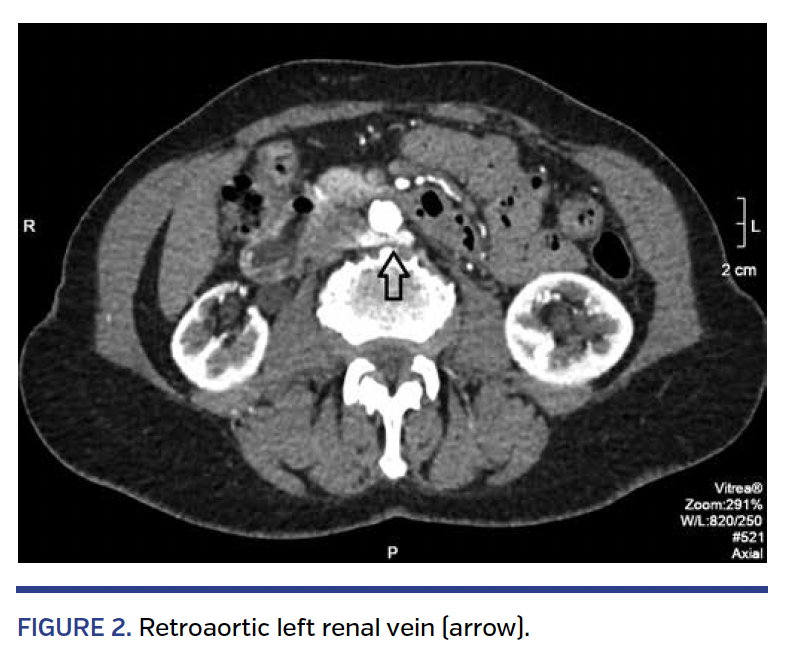

Anomalies of the IVC can be divided into four groups: prerenal, renal, postrenal, and multisegmental. The prerenal anomalies result from atresia or failure to unite the right subcardinal vein with the hepatic vein, leading to infrahepatic IVC interruption and drainage through the azygous vein. The renal anomalies are secondary to a persistent circumaortic venous ring (renal venous collar) or persistence of the dorsal limb but regression of the ventral limb of the circumaortic ring (retroaortic left renal vein) (Figure 2). The postrenal anomalies result from persistence of right and left supracardinal veins (double inferior vena cava [DIVC]) (Figure 3), persistence of left but regression of right supracardinal vein (left IVC), and persistence of right posterior cardinal vein (retroureteral IVC).2-5

DIVC and lower-extremity swelling and pain. DIVC can be associated with left lower-extremity swelling and discomfort if the DIVC is small in size or if the left renal vein is retroaortic (Figure 2) and significantly compressed, leading to an outflow obstruction to the anomalous left IVC that typically drains into the left renal vein.